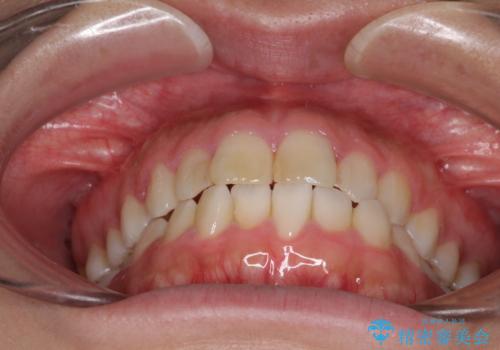

気になる前歯を治したい インビザラインで気づかれずに矯正治療

- ワイヤーではない矯正治療があると聞いたとのことで来院された患者様です。

長年前歯のデコボコを気にしていたもののワイヤー矯正に抵抗があり躊躇していたそうですが、インビザラインなら治療してみたいとのことで相談にいらっしゃいました。

インビザライン適用の歯列であったため、歯と歯の間を削るIPRを用いて改善することとしました。

お仕事柄、長時間のマウスピース装着が苦ではなかったので、歯列はすぐに整いましたが、ゆっくりとした交換頻度であったので、2年ほどの治療期間を要しました。